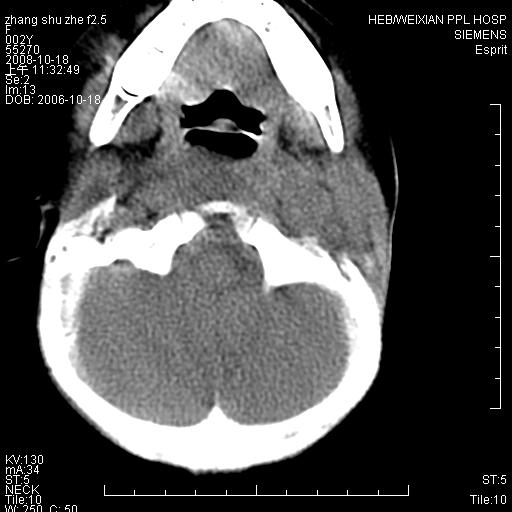

以下是引用dyqct在2009-2-10 21:04:00的发言:[br]年龄?性别?有发烧吗?[br]鼻咽部、口咽部、喉咽部及颈椎前间隙广泛肿厚,明显占位效应并致相应组织变形。ct值22-28hu。[br]考虑:1、颈前脓肿可能性大;[br] 2、建议增强或治疗后复查。

以下是引用jiangjing在2009-2-11 11:37:00的发言:[br]急性病程,鼻咽部、口咽部、喉咽部及颈椎前间隙广泛肿厚,明显占位效应并致相应组织变形.考虑颈部感染性病变(脓肿?);建议行进一步检查。